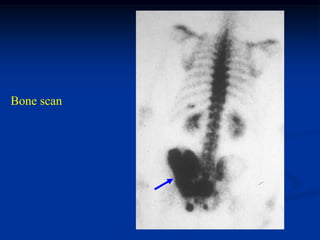

Case #1167                       CT scan

56 year female with bone island looking like blastic metastasis

Negative bone scan suggests a pseudotumor diagnosis